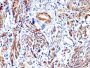

IHC, FFPE (verified), WB (verified)

Positive Control

Uterus, Blood vessels in all tissues, smooth muscle or leiomyosarcoma

Antibody applications

IHC (FFPE) (verified)|WB (verified)